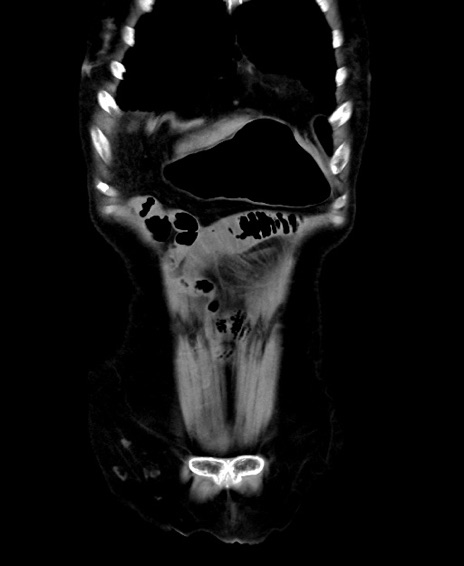

症例40(冠状断像)他院1日前

他院CT